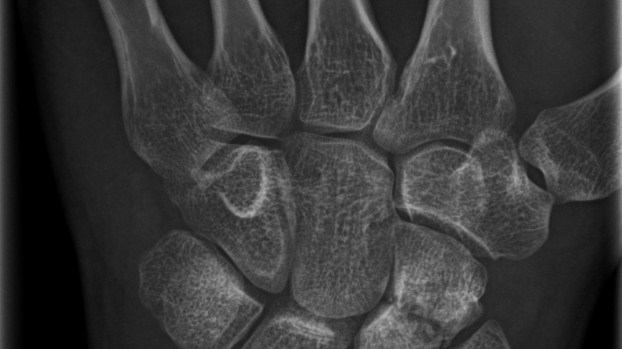

Bennetfraktur

Bennetfraktur är en intraartikulär luxationsfraktur genom basen av metacarpale I. Metacarpalbasen tenderar att luxera genom APL senans dragning i radiell-proxmal riktning. Frakturen behöver därför i princip alltid reponeras och immobiliseras internt med stift. Kan se väldig beskedlig ut på primära bilder men dislocerar succesivt genom senans dragning – klassificeras därför som ”lurig”.

Mekanism vid Bennetfraktur

Bennetfraktur där det ulnara fragmentet i basen på metkarpalen hålls kvar med hjälp av ligament i karpus. På grund av drag i abductor pollicis longus (APL) uppstår nästan alltid en diastas i frakturen. Diastasen i ledytan ger sekundärt artros. Dessa frakturer kräver således exakt fixation – vanligen i form av stift eller skruv.